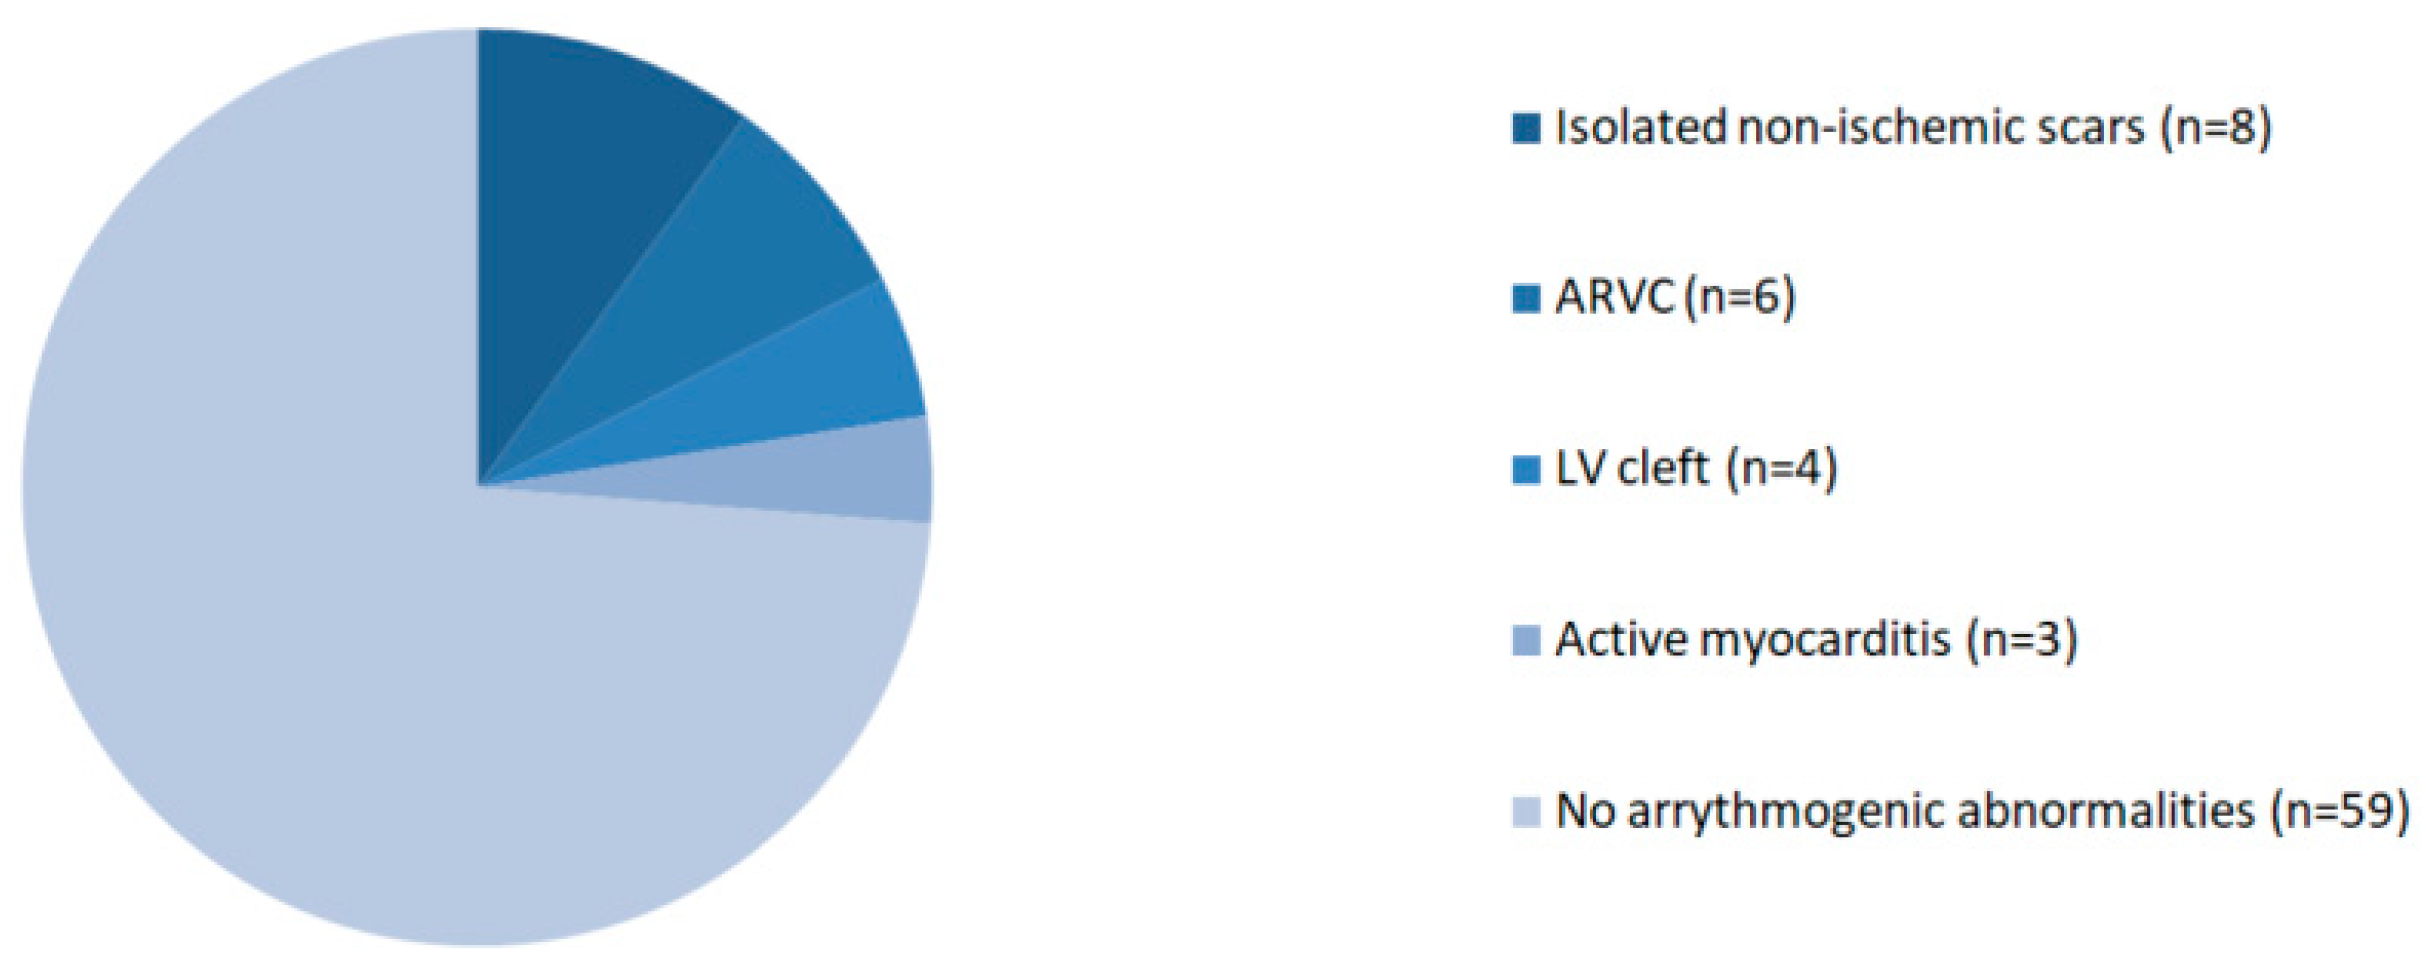

3.2. CMR Findings